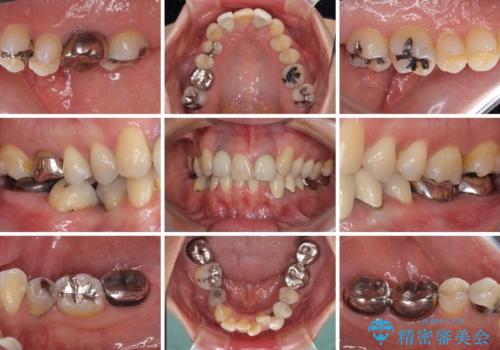

- 非対称な前歯や奥歯の目立つ銀歯を気にして来院された患者様です。

左上前から2番目の歯は、以前裏側に位置していたことから抜歯をされていましたが、前歯の非対称が長年気になっているとのことでした。

他にも奥歯の咬み合わせに問題があったので、全顎的な矯正治療を行い、前歯以外にも口を開けたときに目立つ奥の銀歯をセラミッククラウンにて補綴治療を行うこととしました。